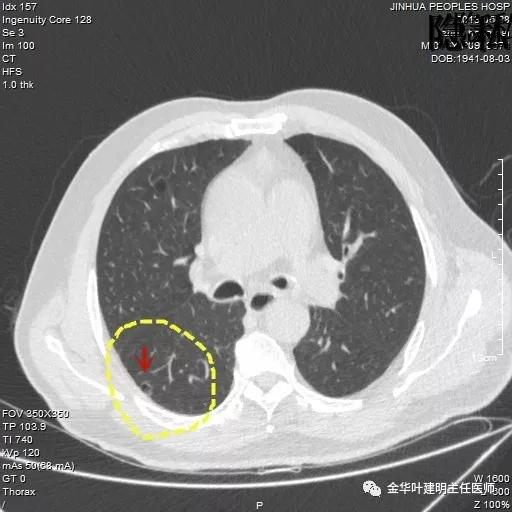

以上是2015年12月的片子,此处没有异常。

以上是2016年5月的片子,此处有非常小而淡的空腔性病灶,边缘略显磨玻璃,但仍说不上肯定的恶性。